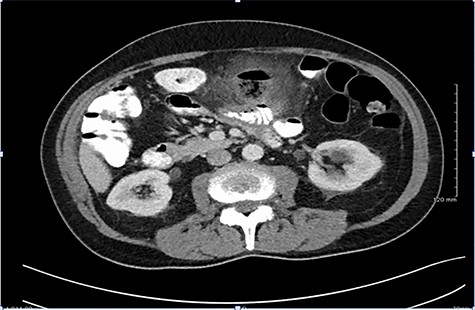

CT findings demonstrating large inflammatory mass related to perforated jejunal diverticulitis.

A computer tomography (CT) scan of his abdomen and pelvis with oral and intravenous contrast was performed on Day 1 of admission (Fig. 1). CT revealed a large inflammatory mass/abscess cavity containing gas and faecal like content, located centrally in the upper abdomen. The abnormality measured 3.7 x 3.8 x 3.9 cm. There was considerable stranding of surrounding mesentery with thickening of adjacent small bowel and appearances were consistent with a small perforation. His CRP had risen on Days 1 to 243 from 92.3 and he had continued to spike temperatures throughout the day (38.6 and 38.4°C) despite commencement of broad spectrum empirical antibiotic therapy.